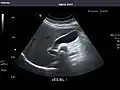

Abdominal ultrasound can be used to diagnose abnormalities in various internal organs, such as the kidneys,[1] liver, gallbladder, pancreas, spleen and abdominal aorta. If Doppler ultrasonography is added, the blood flow inside blood vessels can be evaluated as well (for example, to look for renal artery stenosis). It is commonly used to examine the uterus and fetus during pregnancy; this is called obstetric ultrasonography.[2][3]

Kidneys: Right and left kidneys measure 11.5 cm and 12 cm in length respectively. No hydronephrosis. Small left lower pole kidney cyst.